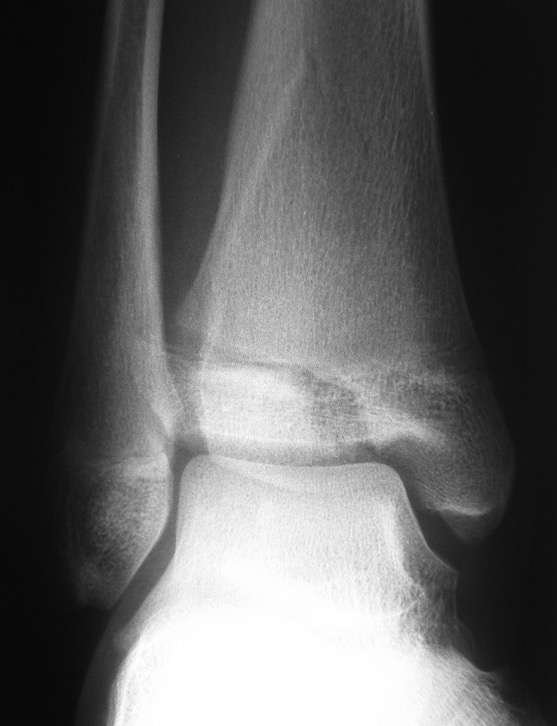

Triplanar Fracture

Definition

Fracture in coronal, sagittal and transverse planes

- crosses epiphysis

- passes through growth plate

- extends into metaphysis

Xray

AP xray: Salter-Harris type III / Tillaux

Lateral xray: Salter-Harris Type II

CT

Coronal images: Salter-Harris type III

Sagittal images: Salter-Harris type II

Axial images: 3 point star